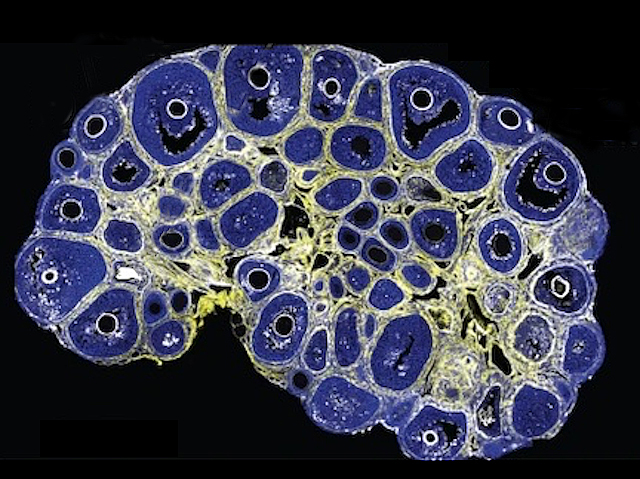

Before an egg can set out with a chance to meet a plucky sperm cell, a series of complex developmental steps must go off without a hitch. Researchers investigating this early stage of development have honed in on the forces driving follicle development. Each follicle is a small sack in the ovaries with an immature egg. As they mature, a fluid-filled space called the antrum grows, and advanced microscopy, machine learning, and theoretical modelling is helping scientists track this change (follicles at different phases of maturity pictured, with the most developed showing the characteristic ‘smiley face’ antrum – a sign that a follicle may be nearly ready to break open and release an egg). A failure to release eggs is a hallmark of infertility in ageing and diseases such as polycystic ovary syndrome, so understanding the physical and biological forces at play could point researchers towards practical solutions.